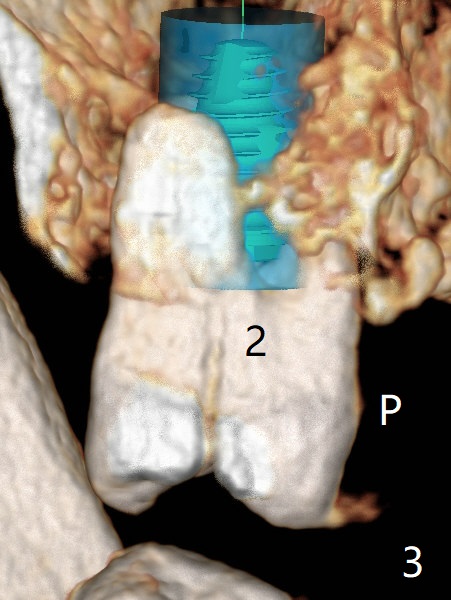

After implant placement at #13 six months post bone graft (Fig.1), reexami-nation shows that the tooth #2 cracks (Fig.2-4). The bony defect area is easier to identify with CT (between MB and P roots of #2) than without CT (M) for #13. There is no bone height reduction after extraction of #15 (Fig.5). Due to new coronal virus outbreak, the patient wants extraction first. The sinus floor perforates (*) apical to MB (Fig.6) and DB (Fig.7) roots. After debridement, sinus lift will be conducted using allograft hydrated with GEM21S liquid portion. The same mix will be used for socket preservation. With high concentration of growth factor, it is hoped that bone density in the sockets will increase quick and high enough for future implant, as compared to #13 of the same patient.